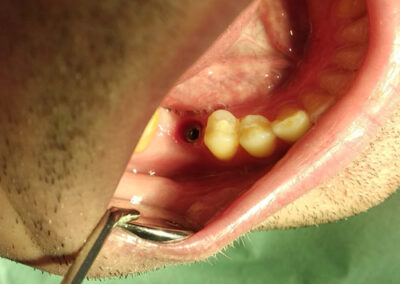

Pacijentu je nedostajao prvi molar u bočnoj regiji. Ovaj zub je posebno značajan i njegov nedostatak narušava kontinuitet celog zubnog luka. Imajući u vidu da su susedni zubi bili zdravi, kao idealno rešenje sa pacijentom je dogovorena ugradnja implanta i protetska nadoknada na implantu.

Na rendgen snimcima prikazana je donja vilica pre ugradnje implanta i donja vilica nakon perioda srastanja (oseointegracije) implanta sa koštanim tkivom.